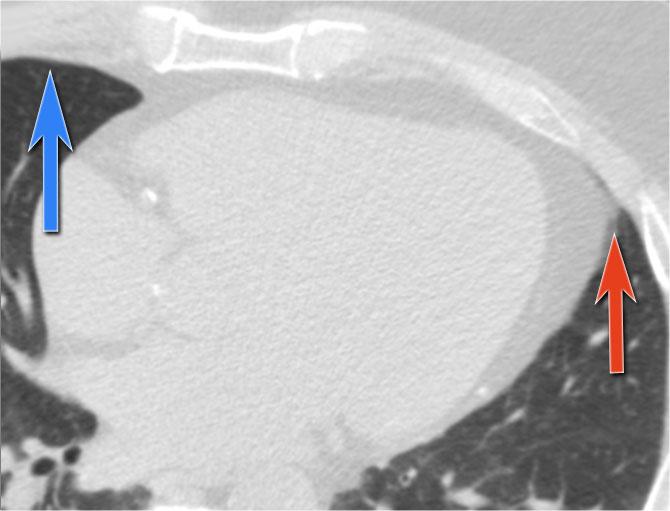

Ca Lâm Sàng 2 – Hình ảnh CT

- CT cho thấy tràn dịch màng ngoài tim sau lượng lớn đang chèn ép thất trái (mũi tên xanh dương: dịch tràn; mũi tên đỏ: thất trái bị chèn ép, có ngấm thuốc cản quang).

- Phẫu thuật thám sát xác nhận khối máu tụ màng ngoài tim sau lớn.

Lưu ý: Lượng dịch tối thiểu ở phía trước trên siêu âm có thể đánh giá thấp thể tích thực sự nếu dịch tràn khu trú ở phía sau, nhấn mạnh giá trị của CT trong các trường hợp sau phẫu thuật.

Đặc biệt ở những bệnh nhân vừa trải qua phẫu thuật tim, sự to ra của bóng tim có thể là dấu hiệu của chảy máu màng ngoài tim.

Bệnh nhân này có sự thay đổi hình dạng tim (tầm quan trọng của hình ảnh trước đó) và chảy máu màng ngoài tim được nghi ngờ.

Siêu âm chỉ phát hiện tràn dịch màng ngoài tim tối thiểu.